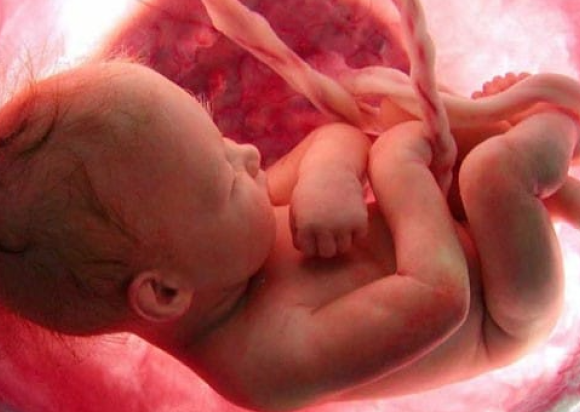

Managing Health Concerns Of The Mother And Fetus Prior To, During, And Shortly After Pregnancy.

Our specialized team of doctors at ASMEE performs tests on the fetus to screen for health problems, presides over ultrasound examinations, and attempts to treat birth defects, disorders, and infections. Facilities like 4D ultrasonography, amniocentesis, etc helps in early detection and timely intervention helping the delivery of a healthy baby.

Fetal medicine is speciality where specialists look at yourbaby in uterus and make sure your baby is developing in proper manner structurally and also achieving its growth potential.